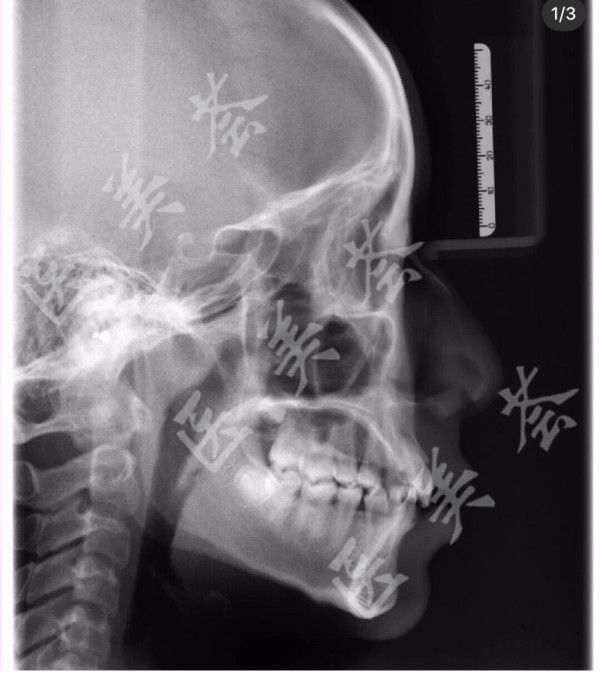

口腔侧位片

侧位片.jpg

图片尺寸580x443

赤壁二医院口腔科技术资料留存